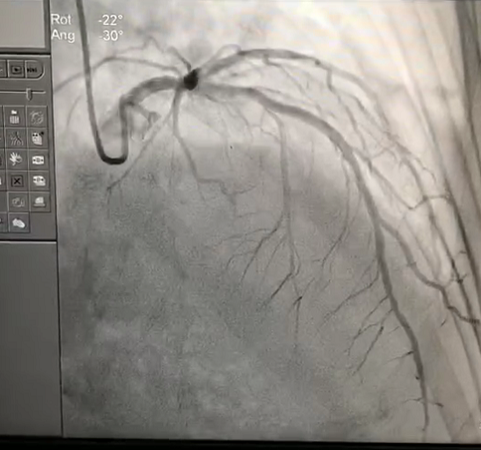

患者冠脉造影图

患者为53岁女性,6月前降支近端植入支架一枚,近2月频繁出现胸闷憋气等不适,偶有晕厥症状出现。心脏超声显示LA49mm,LV41mm,IVS14mm,PW16mm,LVEF0.51,E峰>2A峰,平均E/e’27.7,超声显示为舒张性心衰表现,T-proBNP3540pg/ml,经实施超声指导下的经桡动脉左心室心内膜心肌活检术后,病理确诊为心肌淀粉样变。